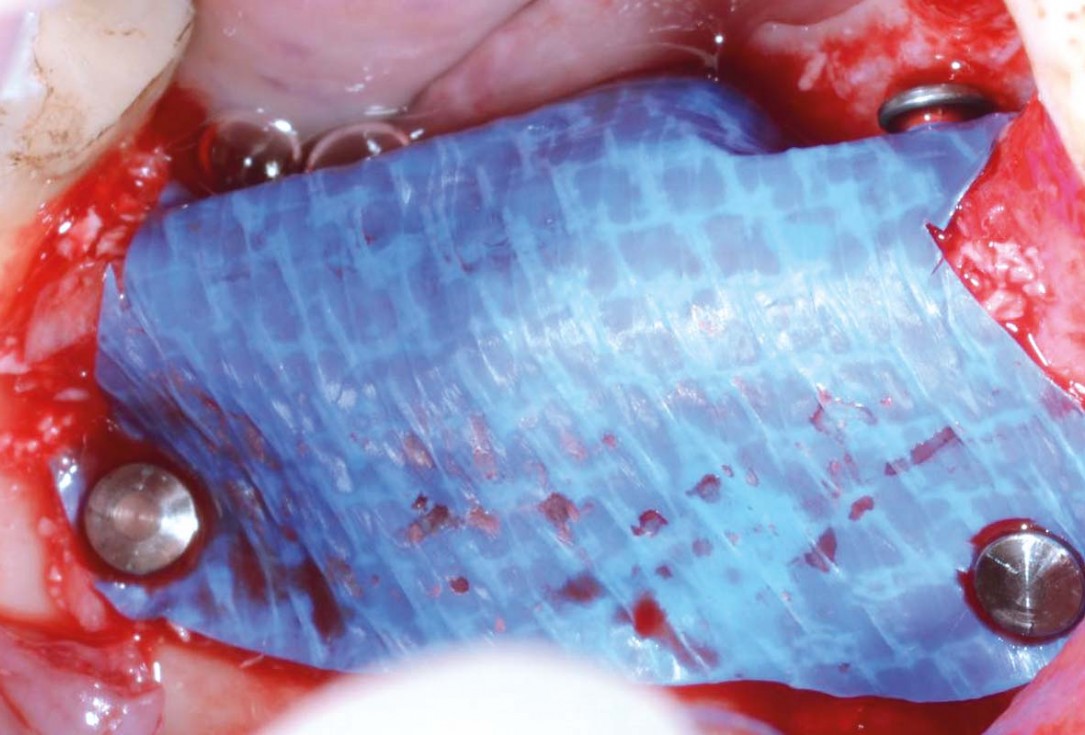

07/29 - Covering of the augmented area and buccal fixation of permamem® with titanium pinsVertical bone augmentation and broadening of attached gingiva using cerabone®, permamem® and mucoderm® - Dr. R. Naimoli